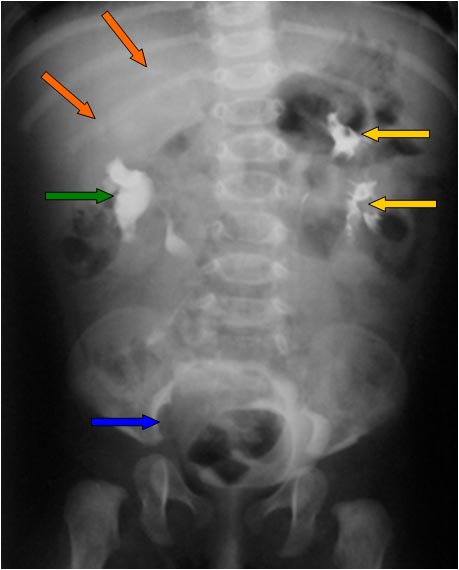

SIGNOS DE LA COLMENA Y DEL HERALDO

Signos de fístula colovesical en la cistografía. El extremo vesical de la fístula se asocia con la imagen de una deformidad biconvexa triangular (flechas verdes) que acaba en un punto bien definido, como si se insinuase el contraste en la boca de la fístula. De hecho puede verse contraste fuera de la vesícula, por encima de ese ángulo que forma el borde superior vesical.

En nombre del Signo de la colmena se debe a que la vejiga queda deformada adoptando una forma que recuerda a la celda de una colmena.

El Signo del heraldo es un signo temprano visible en el borde superior de la vejiga, en forma de semiluna. Es un hallazgo descrito en 1961 del que no hemos encontrado imágenes. Hemos marcado con flecha roja el borde semilunar de la vejiga, pero no sabemos si se trata en realidad de este hallazgo.